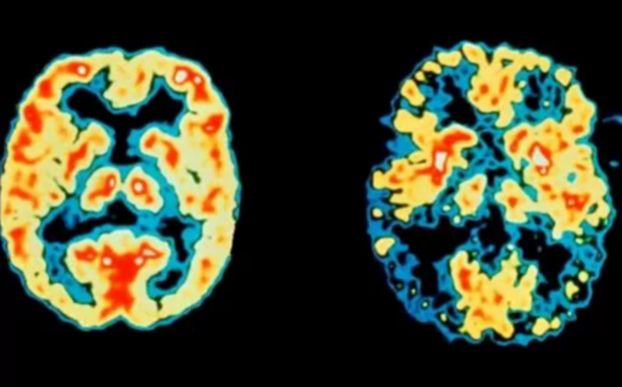

أفادت دراسة علمية بأن الجزء الموجود في دماغ الإنسان المسؤول عن التعرف على الوجوه، يواصل نموه مع تقدم الانسان في العمر، على عكس ما اعتقده العلماء بأنه يتوقف نموه في مراحل مبكرة. واكتشف الباحثون من خلال تقنية التصوير بالرنين المغناطيسي لأدمغة أطفال وكبار، أن المنطقة من القشرة الدماغية التي تؤدي على الارجح دوراً أساسياً في التعرف على الوجوه والمسماة تلفيف الدماغ، تواصل النمو حتى بين الكبار، وفق ما جاء في موقع «ساينس دايلي». وشملت الدراسة 47 شخصاً، من بينهم 22 طفلاً بين الخامسة والثانية عشرة، أما الباقون بين سن الثانية والعشرين والثامنة والعشرين.

وخلّص الباحثون إلى أن تلفيف الدماغ لدى الكبار كان اكثر نمواً بنسبة 12.6 في المئة من الصغار. وقالت استاذة علم النفس في معهد علوم الأعصاب في جامعة ستانفورد كالانيت غريل سبكتور إن هذا الاكتشاف سيسهل فهم بعض مظاهر الشيخوخة والصعوبة لدى بعض الاشخاص في التعرف على الوجوه، وهو ما يصيب شخصاً واحداً من بين كل 50 شخصاً بالغاً. وأوضحت سبكتور أن الدراسة ستفيد في فهم اضطرابات التوحد التي يمكن أن تؤثر في القدرة على التعرف على الوجوه.